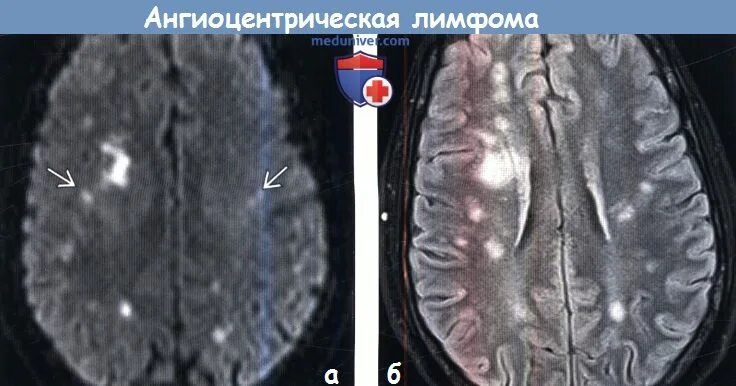

Очаг ограничения диффузии